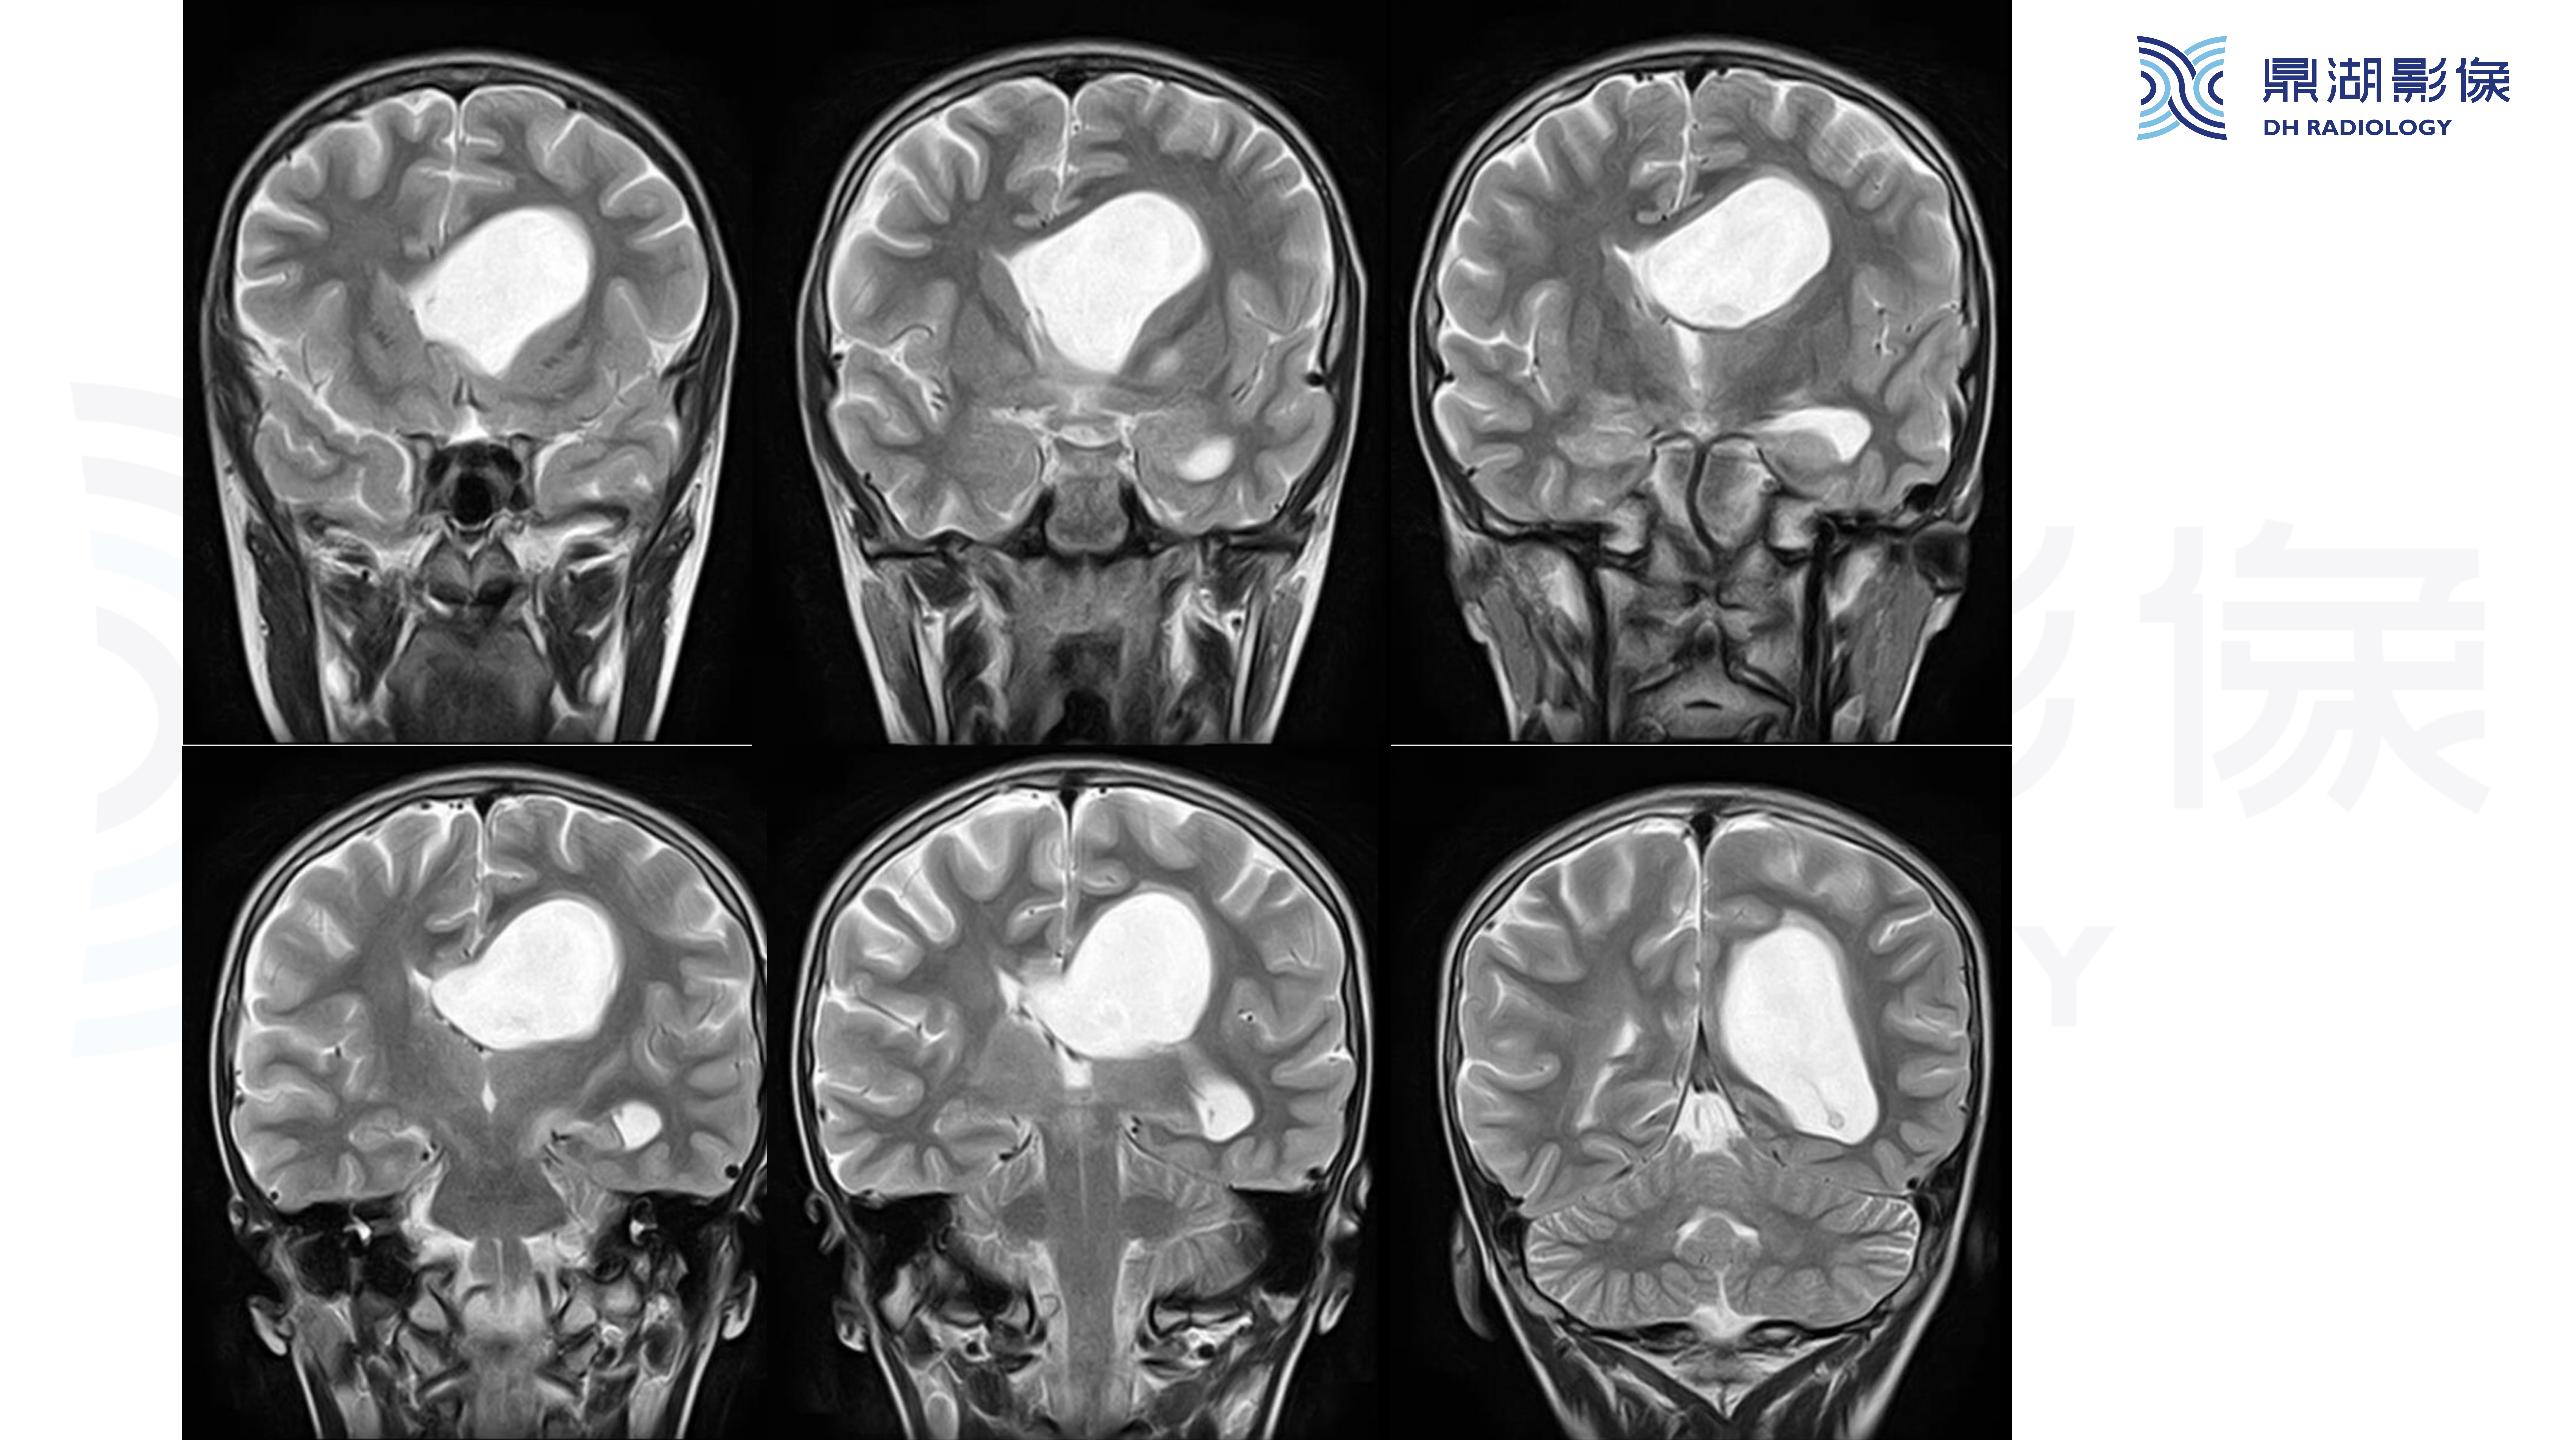

裂隙脑室综合征 (slit ventricle syndrome,SVS)-鼎湖社群读片病例